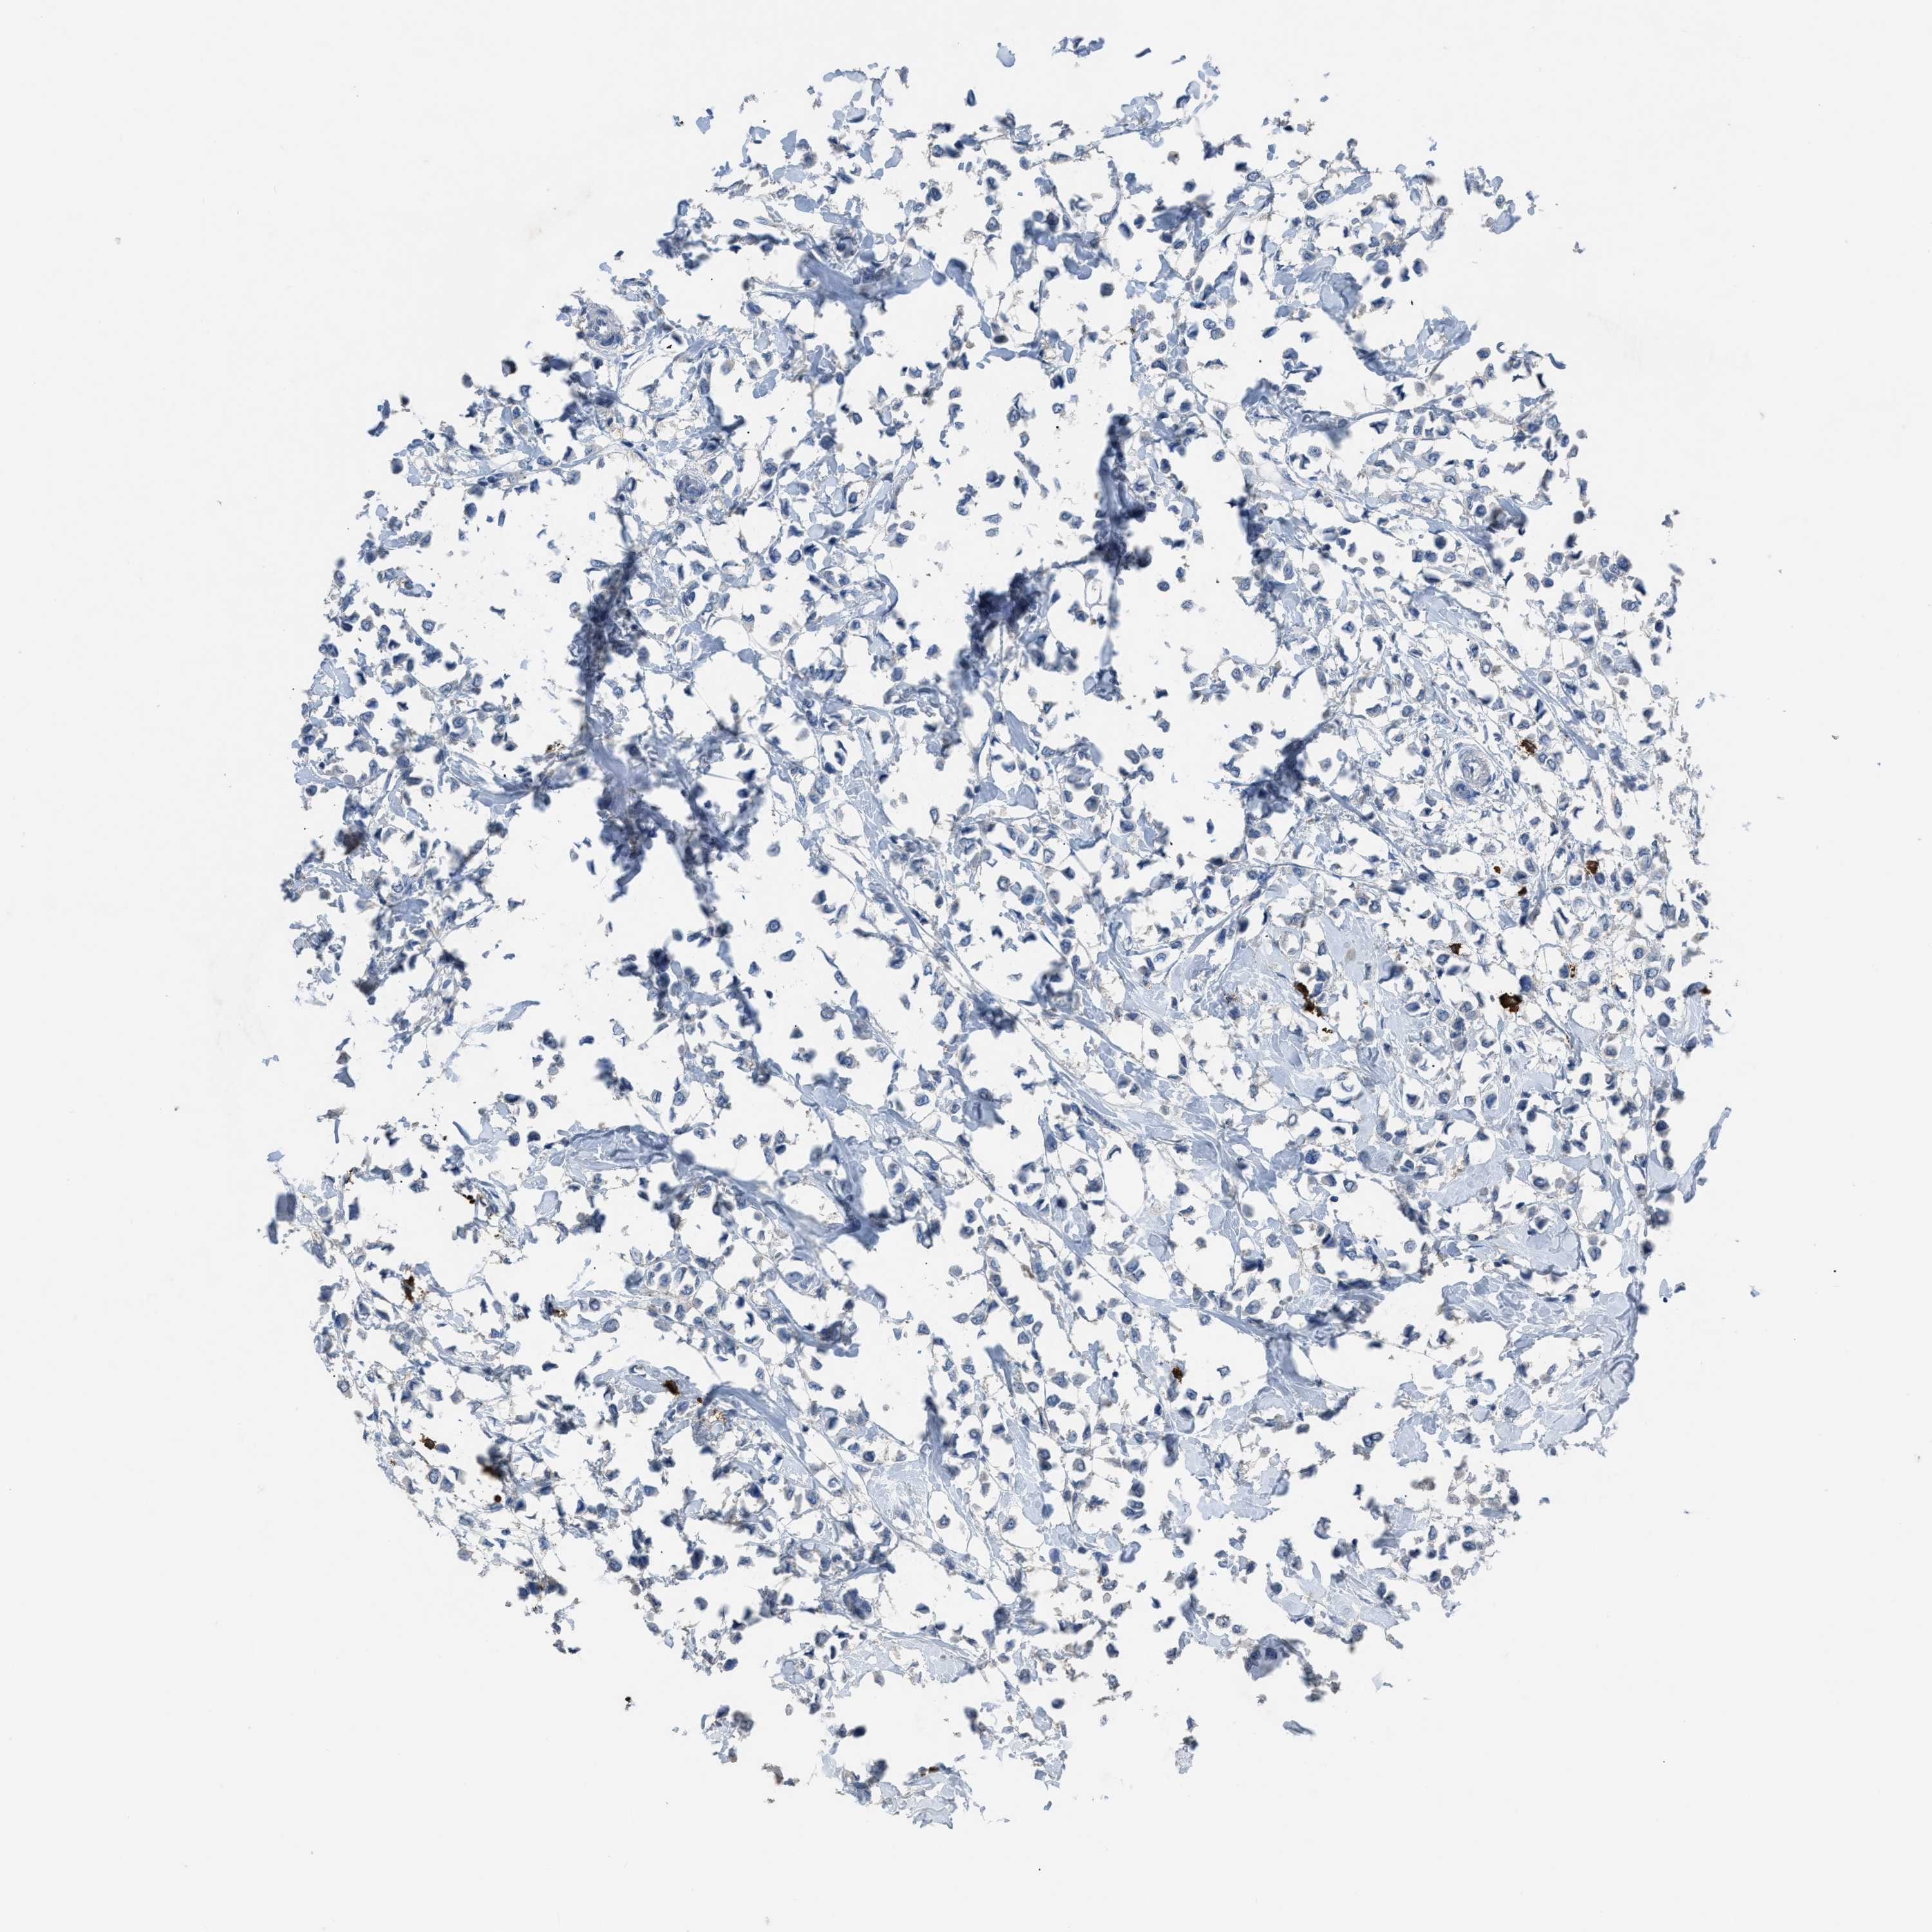

BRCA TCGA BRCA VALIDATION PROTEIN EXPRESSION

ANTIBODIES

AND

VALIDATION